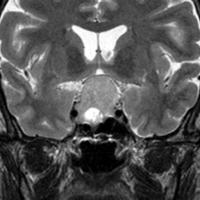

とても小さな腫瘍(微小腺腫) microadenoma

1cm以下の小さなものを微小腺腫といいます。ホルモンを異常に分泌する腫瘍は摘出する必要がありますが,そうでないものは治療の必要がありません。微小腺腫を数年観察しても増大する確率は10%くらいです。逆に,それ以上に大きなものだと,50%くらいの確率で増大します。

日本で汎用されているものでは最も解像力が高い3テスラMRIで撮影された,ガドリニウム増強像です。左側の画像では下垂体の大きさと形は正常に見えます。画像を調整すると,下垂体の内部,右端(黄色の矢印の先)に6mmくらいの小さな腺腫がみつかりました。MRIの性能がよくなったことによって数mmの小さなものも診断できるようになりました。